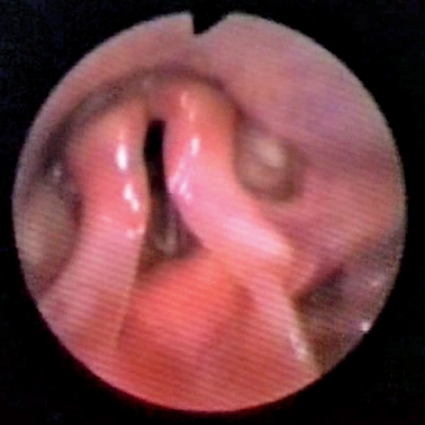

I vårt material hade många patienter supraglottisk obstruktion, och dessa kan i vissa fall opereras med framgång. Vårt material växer stadigt, och vi ser olika bilder av supraglottisk kollaps (Figur 1 och 2), ibland glottisk adduktion (Figur 3) eller en kombination av dessa (Tabell I). I de fall där man påvisar glottisk adduktion (EI-VCD) kan operation inte rekommenderas, och det är ovisst om vi i framtiden kan erbjuda dessa patienter någon hjälp. Andningsteknik i samråd med logoped och/eller sjukgymnast [11] är en möjlig väg att gå, men effekten är svår att utvärdera.